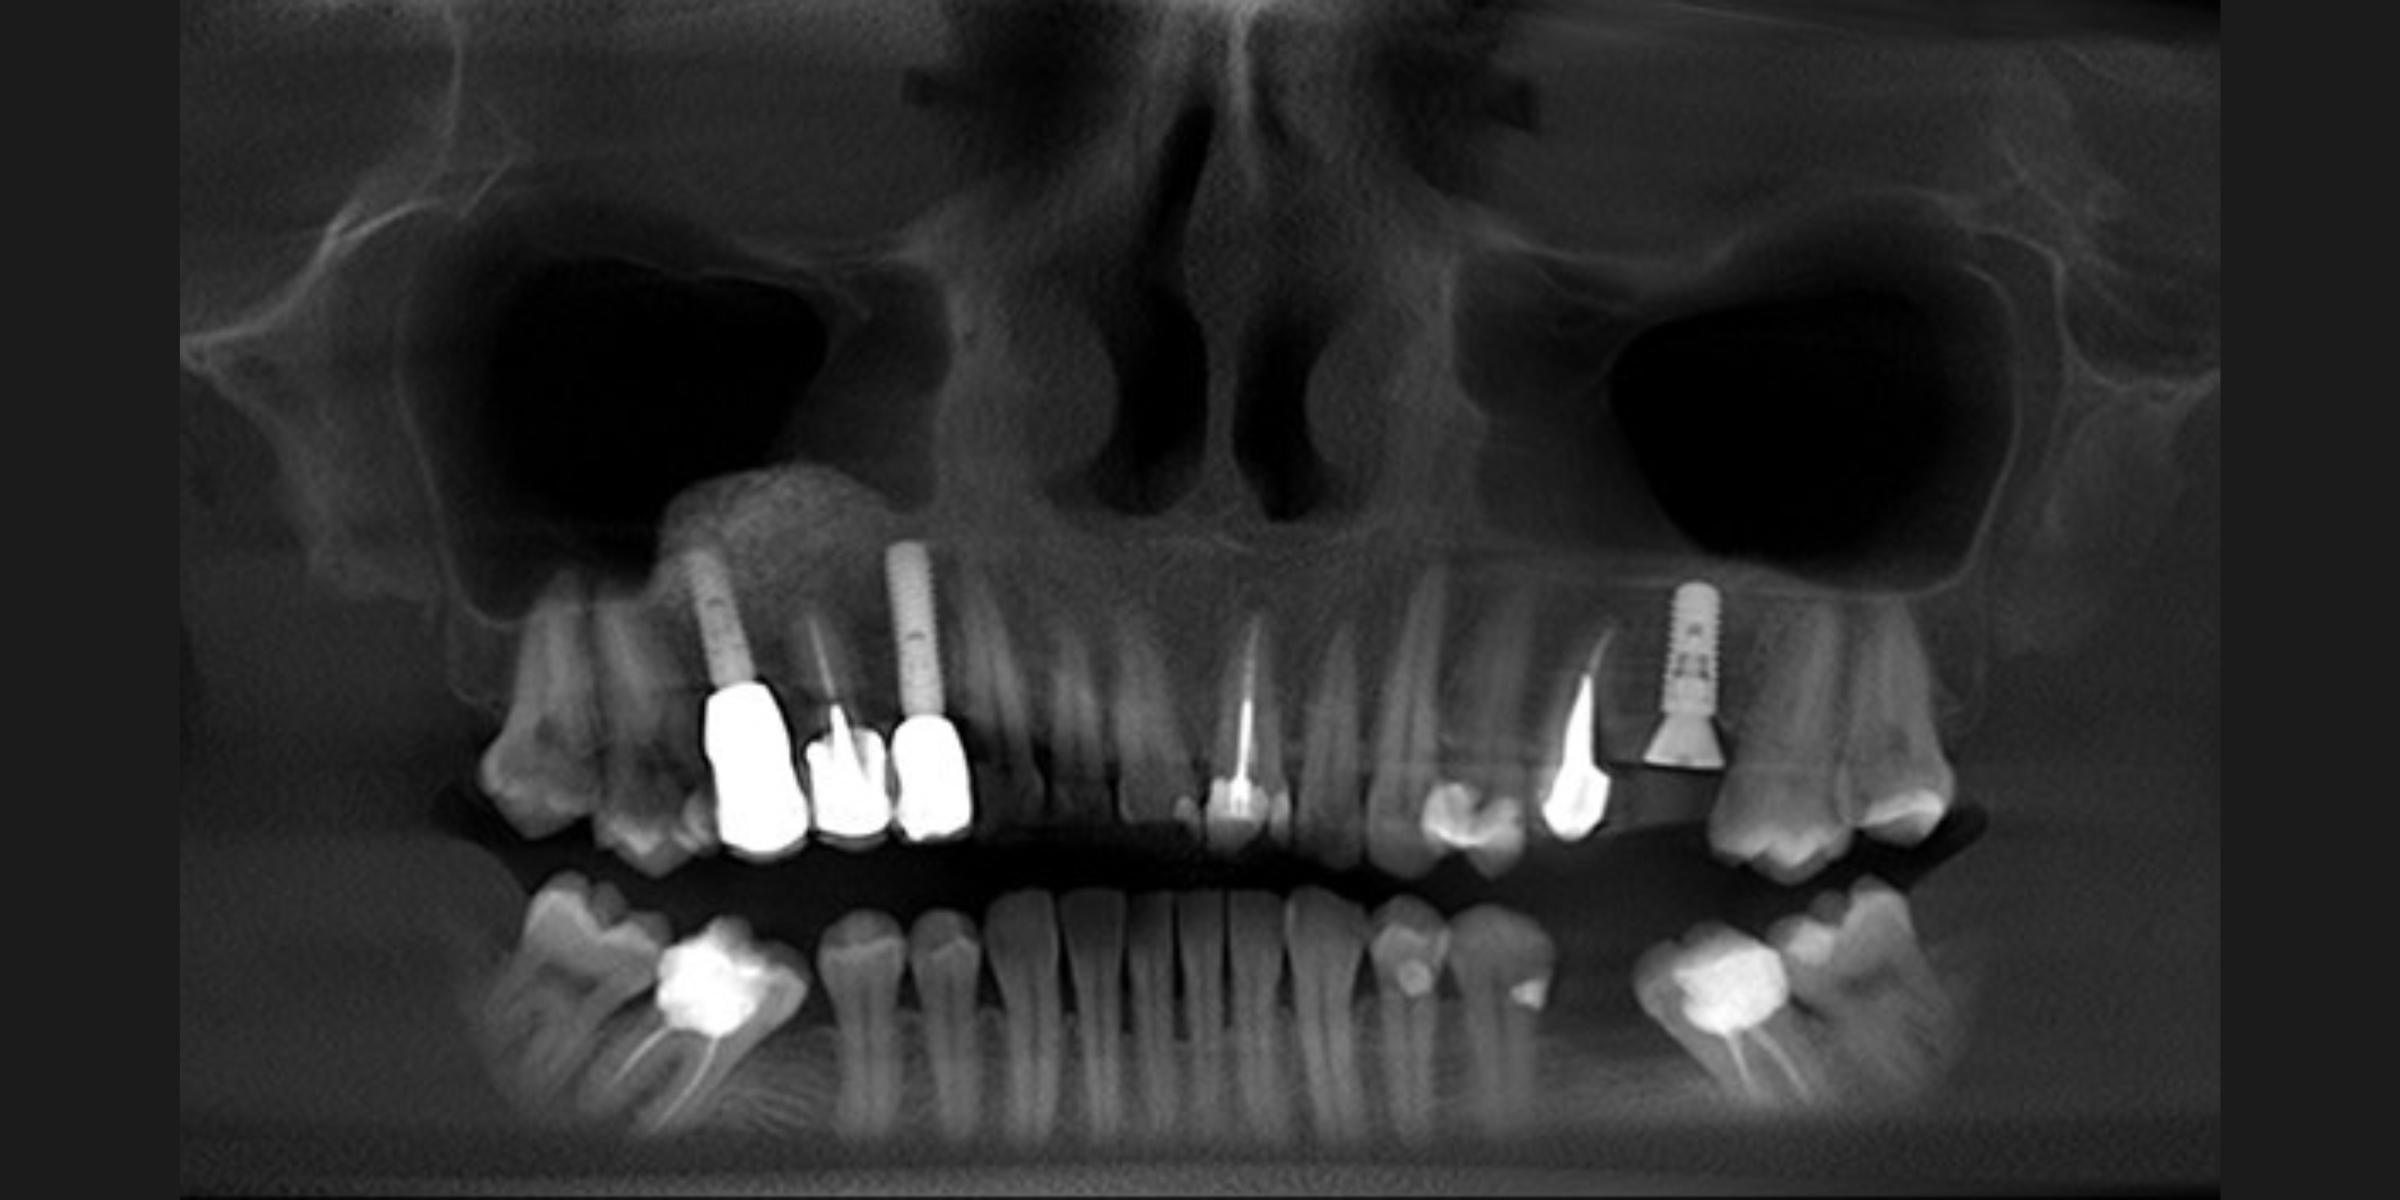

The increasing demand for efficient and minimally invasive tooth replacement options has driven the adoption of immediate implant placement. Within the framework of a patient-centered and comprehensive treatment plan, selecting the appropriate timing for implant placement is a crucial determinant of overall treatment success. Unlike delayed implant placement, which requires several months of healing after extraction, IIP involves placing the implant directly into the fresh extraction socket (Figures 1 and 2). This technique not only reduces the number of surgical interventions and associated patient morbidity but also allows for immediate implant-supported fixed restorations if conditions permit. It significantly reduces both chair time and overall treatment duration compared to other protocols (Puisys et al., 2022). Advances in surgical protocols, digital diagnostics, and implant design have made IIP increasingly predictable, particularly when combined with immediate temporization. However, the clinician must weigh these benefits against the increased technical demands and biological complexities inherent in the procedure. The ITI SAC Classification Tool (Straightforward, Advanced, Complex) helps stratify cases by risk and complexity, thereby guiding appropriate case selection and operator readiness (Morton et al., 2023).

Fig. 1a: CBCT of initial situation with non-restorable tooth 21

Fig. 1b: Initial situation with non-restorable tooth 21

Fig. 2: Implant placed into the fresh extraction socket in the correct 3D position ( Straumann BLX Roxolide SLActive 3.75×12)